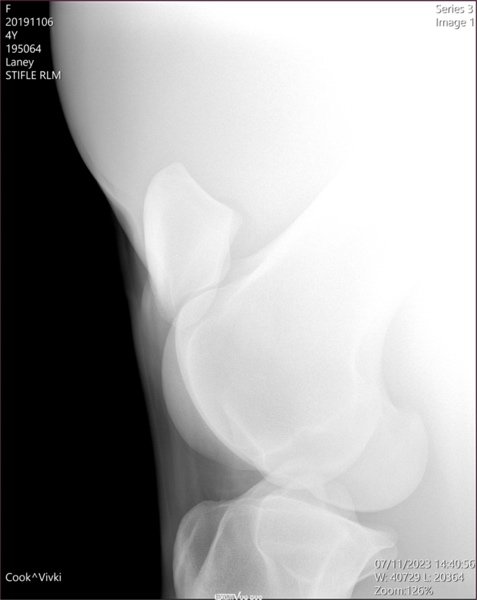

Samples of X-Rays